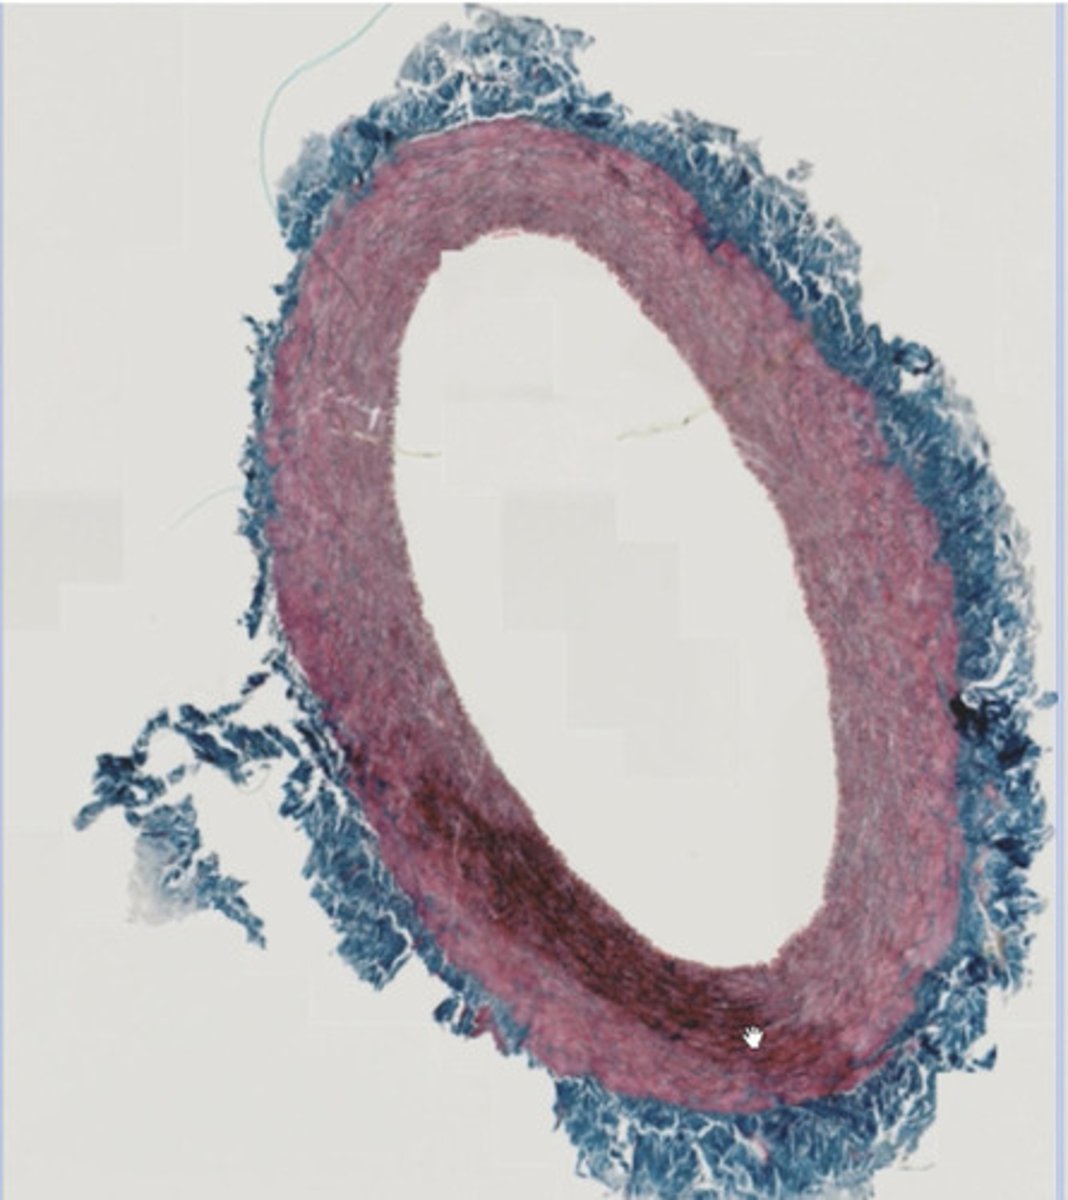

Tętnica typu mięśniowego (met. trójbarwna- azan)